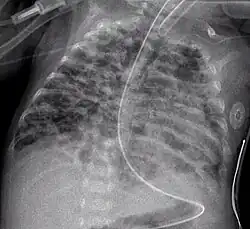

Вторая стадия (4—10-й дни жизни) — ателектазы становятся более распро страненными и чередуются с участками эмфиземы, участки некрозов и репарации эпителия бронхиол, некротические массы заполняют воздухоносные пути. На рентгенограмме грудной клетки — «воздушная бронхограмма», легочные поля местами затемнены, но видны участки интерстициальной эмфиземы;

Третья стадия (11—З0-й дни жизни) — распространенная метаплазия и гиперплазия эпителия бронхов и бронхиол, участки эмфиземы, окруженные зонами ателектаза, массивный интерстициальный фиброз и отек с истончением базальных мембран, альвеол. На рентгенограмме — участки воспаления, зоны ателектазов и появление кист;

Четвертая стадия (2 месяц жизни) — массивный фиброз легких с деструкцией альвеол и стенок воздухоносных путей (с метаплазией эпителия), гипертрофия мышечного слоя бронхиол, уменьшение количества легочных артериол и капилляров с гипертрофией мышечного слоя артериол и венул. На рентгенограмме — массивный фиброз легких с отеком и зонами воспаления, уплотнений.

Диагноз. Общепринятых критериев ранней диагностики БЛД нет. Предложены следующие четыре критерия для диагностики БЛД: • необходимость ИВЛ по крайне мере в течение 6 дней (по нашему мнению, в течение трех дней) на первой неделе жизни (обычно с положительным дав- лением на выдохе и длительным высоким F102); • Рао2 в крови 50 торр (мм рт.ст.) и менее, и для подъема его необходима кис- лородотерапия до возраста более 28 сут. (по Jobe А.Н. и Bancalari E.H., 2001, до 36 нед. гестационного возраста); • хронический респираторный дистресс (одышка, ретракция грудной клетки, дыхательные шумы, выявляемые при аускультации или слышимые на рас- стоянии) и наличие признаков явной дыхательной недостаточности и при- знаков периодического бронхообструктивного синдрома, продолжающихся не менее 28 суток; • торпидные рентгенологические изменения — в легочных полях плотные оча- ги (зоны фиброза) чередуются с зонами повышенной прозрачности, т.е. ги- перинфляции («пчелиные соты»), диафрагма опущена, межреберные проме- жутки расширены, тень сердца увеличена в размерах, контуры сердца неот- четливые, размытые. Согласно A.H.Jobe и Е.Н.Bancalari (2001), выделяют три степени тяжести БЛД: Легкая — потребность в кислородной поддержке до 28-го дня жизни и старше, но ее прекращение до 36 нед. гестационного возраста. Средней тяжести ~ потребность в кислородной поддержке до 28-го дня жизни и старше, но Fio2 <0,3 в 36 нед. гестационного возраста. Тяжелая — необходимость в кислородной поддержке в 36 нед. гестационного возраста с F1O2 >0,3.